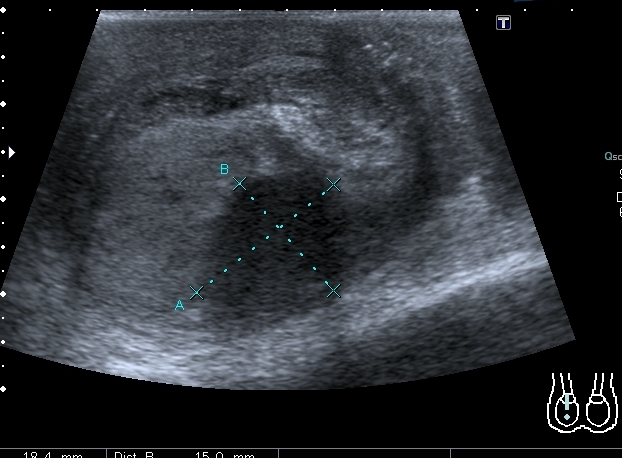

В приёмный покой больницы поступил мальчик 14 лет с жалобами на отёк правой половины мошонки и боли в правом яичке. При УЗИ - правое яичко увеличено отностиельно левого, изменено по структуре, расположено выше левого.